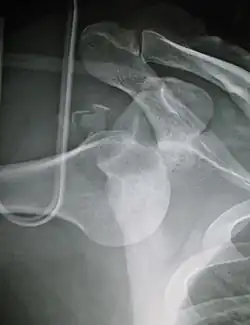

Inferior (downward)

Inferior dislocation is the least likely, occurring in less than 1%. This condition is also called luxatio erecta because the arm appears to be permanently held upward or behind the head.[18] It is caused by a hyper abduction of the arm that forces the humeral head against the acromion.[19] Such injuries have a high complication rate as many vascular, neurological, tendon, and ligament injuries are likely to occur from this mechanism of injury.